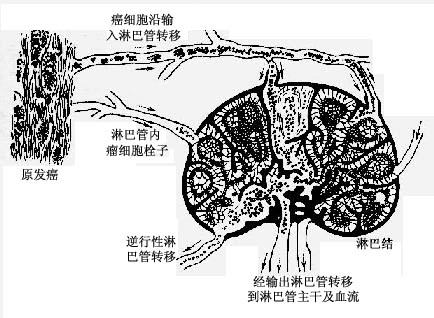

1)淋巴道转移:瘤细胞侵入淋巴管(图7-5)后,随淋巴流首先到达局部淋巴结。例如乳腺外上象限发生的乳腺癌首先到达同侧腋窝淋巴结;肺癌首先到达肺门淋巴结。瘤细胞到达局部淋巴结后,先聚集于边缘窦,以后生长繁殖而累及整个淋巴结(图7-6),使淋巴结肿大,质地变硬,切面常呈灰白色。有时有转移的淋巴结由于瘤组织侵出被膜而互相融合成团块。局部淋巴结发生转移后,可继续转移至下一站的其他淋巴结,最后可经胸导管进入血流再继发血道转移。

图7-5 肿瘤的淋巴道转移

图7-6癌的淋巴道转移模式图

―→淋巴流向 ……→癌细胞流向